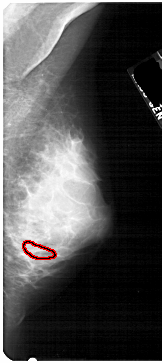

A_1746_1.LEFT_MLO

LEFT_MLO LINES 5491 PIXELS_PER_LINE 2476 BITS_PER_PIXEL 12 RESOLUTION 43.5 NON_OVERLAY

FILE: A_1746_1.RIGHT_MLO.OVERLAY

TOTAL_ABNORMALITIES 1

ABNORMALITY 1

LESION_TYPE CALCIFICATION TYPE PLEOMORPHIC DISTRIBUTION CLUSTERED

ASSESSMENT 4

SUBTLETY 1

PATHOLOGY BENIGN

TOTAL_OUTLINES 1

BOUNDARY